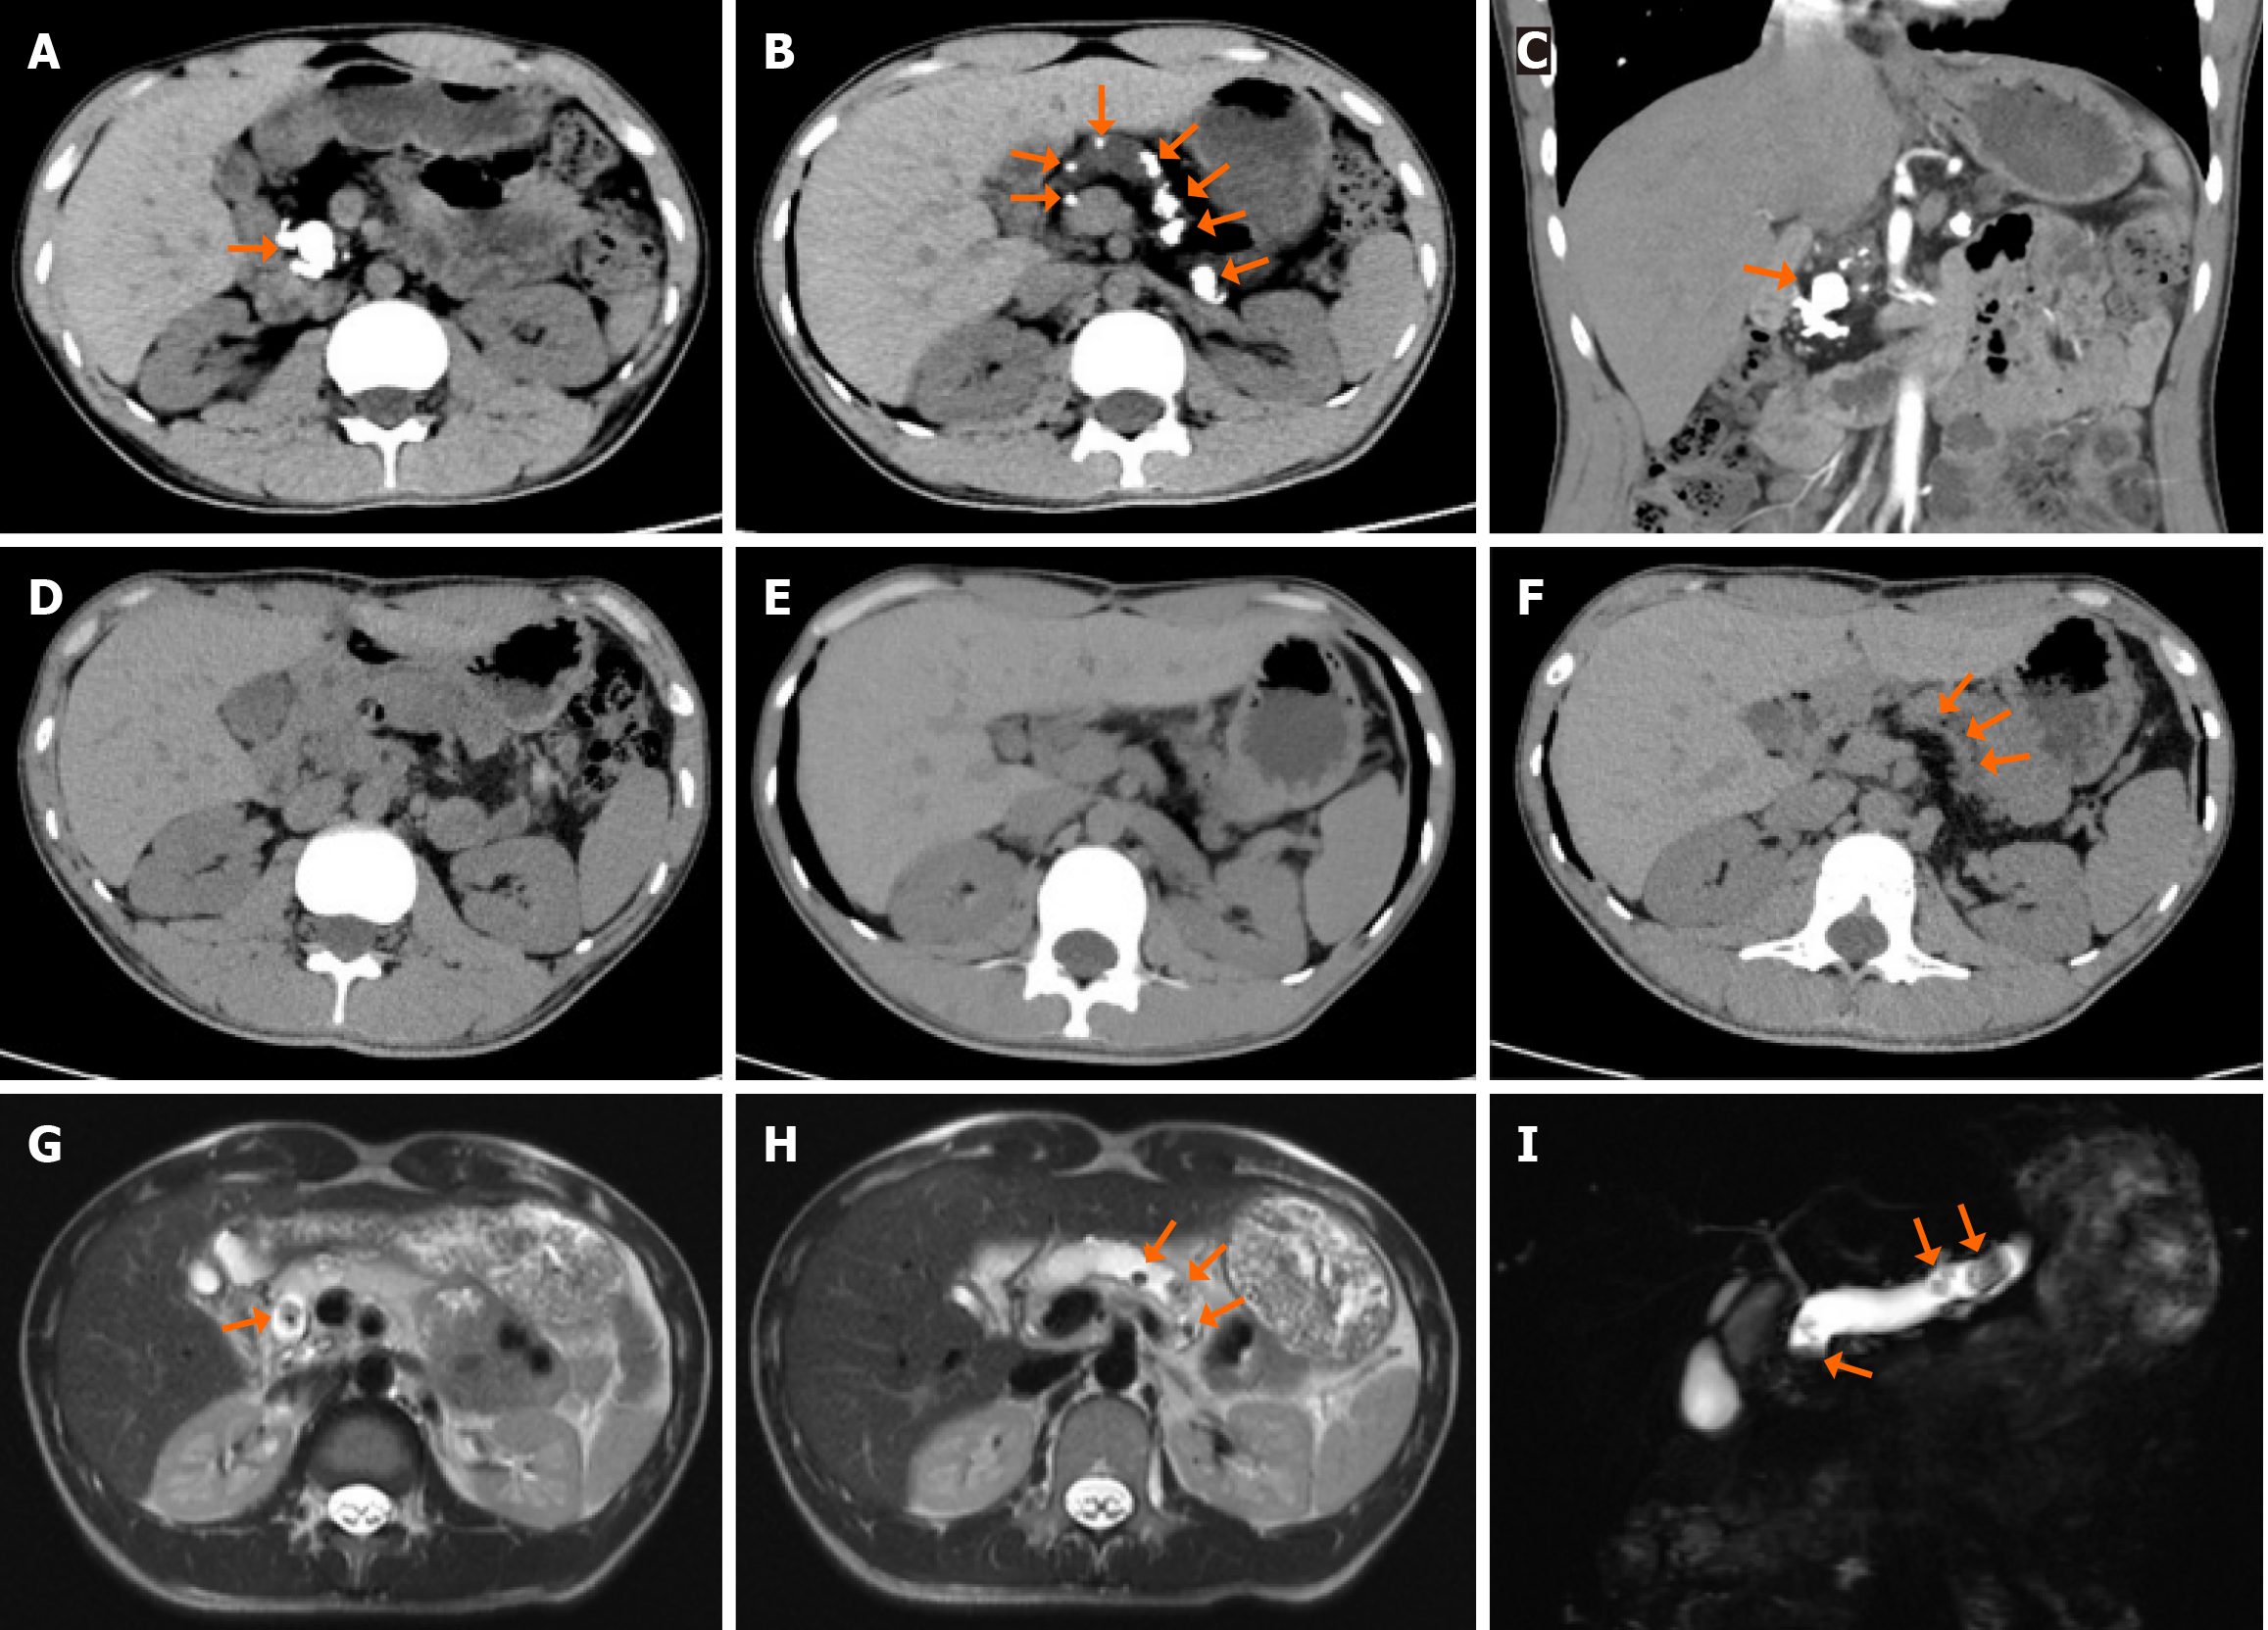

Figure 1 Preoperative and postoperative imaging images.

A: Preoperative plain computed tomography (CT) scan. As indicated by the orange arrows, high-density stones were predominantly located in the pancreatic duct of the pancreatic head; B: Preoperative plain CT scan. As indicated by the orange arrows, multiple high-density stones were scattered in the main pancreatic duct of the pancreatic body and tail; C: Preoperative coronal contrast-enhanced CT scan of the pancreatic head. As indicated by the orange arrows, high-density stones were scattered in the pancreatic duct and pancreatic parenchyma; D: Postoperative plain CT scan of the pancreatic head; E: Postoperative plain CT scan of the pancreatic body and tail; F: Postoperative plain CT scan of the anastomosis. As shown by the orange arrow, no pancreatic duct stones were found at the pancreatic duct-jejunostomy; G: T2-weighted magnetic resonance imaging (MRI) scan of the pancreatic head. As indicated by the orange arrows, a nodular filling defect is observed in the pancreatic duct; H: T2-weighted MRI scan of the pancreatic body. As indicated by the orange arrows, multiple nodular filling defects are observed in the pancreatic duct; I: MRI shows multiple low-intensity signal nodules in the main pancreatic duct.